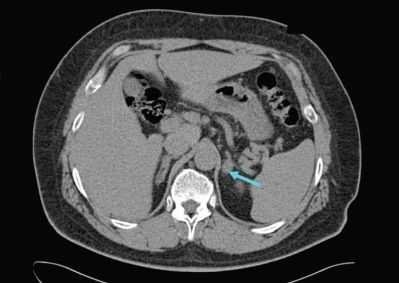

Для пациентов с доказанным первичным гиперальдостеронизмом следующим шагом является выяснение, каким заболеванием он вызван, — односторонним или двусторонним. Это очень важно, так как лечение каждого из них отличается. Компьютерная или магнитно-резонансная томография позволяют увидеть, есть ли опухоль в надпочечнике. Если пациент младше 40 лет и у него есть опухоль только в одном надпочечнике, то в этом случае можно приступать к лечению. Если пациент старше 40 лет и/или у него либо нет опухоли, либо есть опухоль, но в обоих надпочечниках, то возникает необходимость в проведении специального теста — селективного забора венозной крови из центральной вены надпочечников. В ходе этого теста хирург или рентгенолог берёт кровь непосредственно из вен обоих надпочечников, чтобы определить, какой именно орган вырабатывает патологическое количество гормона.

УЗИ надпочечников — низкочувствительный метод диагностики. Предпочтительнее проводить КТ: она помогает выявить как макро- и микроаденомы надпочечников, так и утолщения ножек надпочечников, гиперплазии и другие изменения [14] .

Для уточнения формы гиперальдостеронизма (одностороннего и двустороннего поражения) проводится селективный забор крови из вен надпочечников в специализированных центрах [9] . Это исследование эффективно снижает риск необоснованного удаления надпочечника только по данным КТ [4] .

- Инструментальная визуализация. УЗИ надпочечников и радиоизотопное сканирование (сцинтиграфию) надпочечников используют для выявления имеющихся патологических изменений и уточнения их характера (гиперплазия, опухоль), КТ надпочечников и МРТ надпочечников - для определения локализации и величины альдостеромы.

Для выяснения природы поражения (альдостерома, диффузно-узелковая гиперплазия, рак) используют методы топической диагностики: УЗИ надпочечников, сцинтиграфию, КТ и МРТ надпочечников, селективную венографию с одновременным определением уровней альдостерона и кортизола в крови надпочечниковых вен. Также важно установить заболевание, вызвавшее развитие вторичного гиперальдостеронизма с помощью исследований состояния сердца, печени, почек и почечных артерий (ЭхоКГ, ЭКГ, УЗИ печени, УЗИ почек, УЗДГ и дуплексное сканирование почечных артерий, мультиспиральная КТ, МР-ангиография).